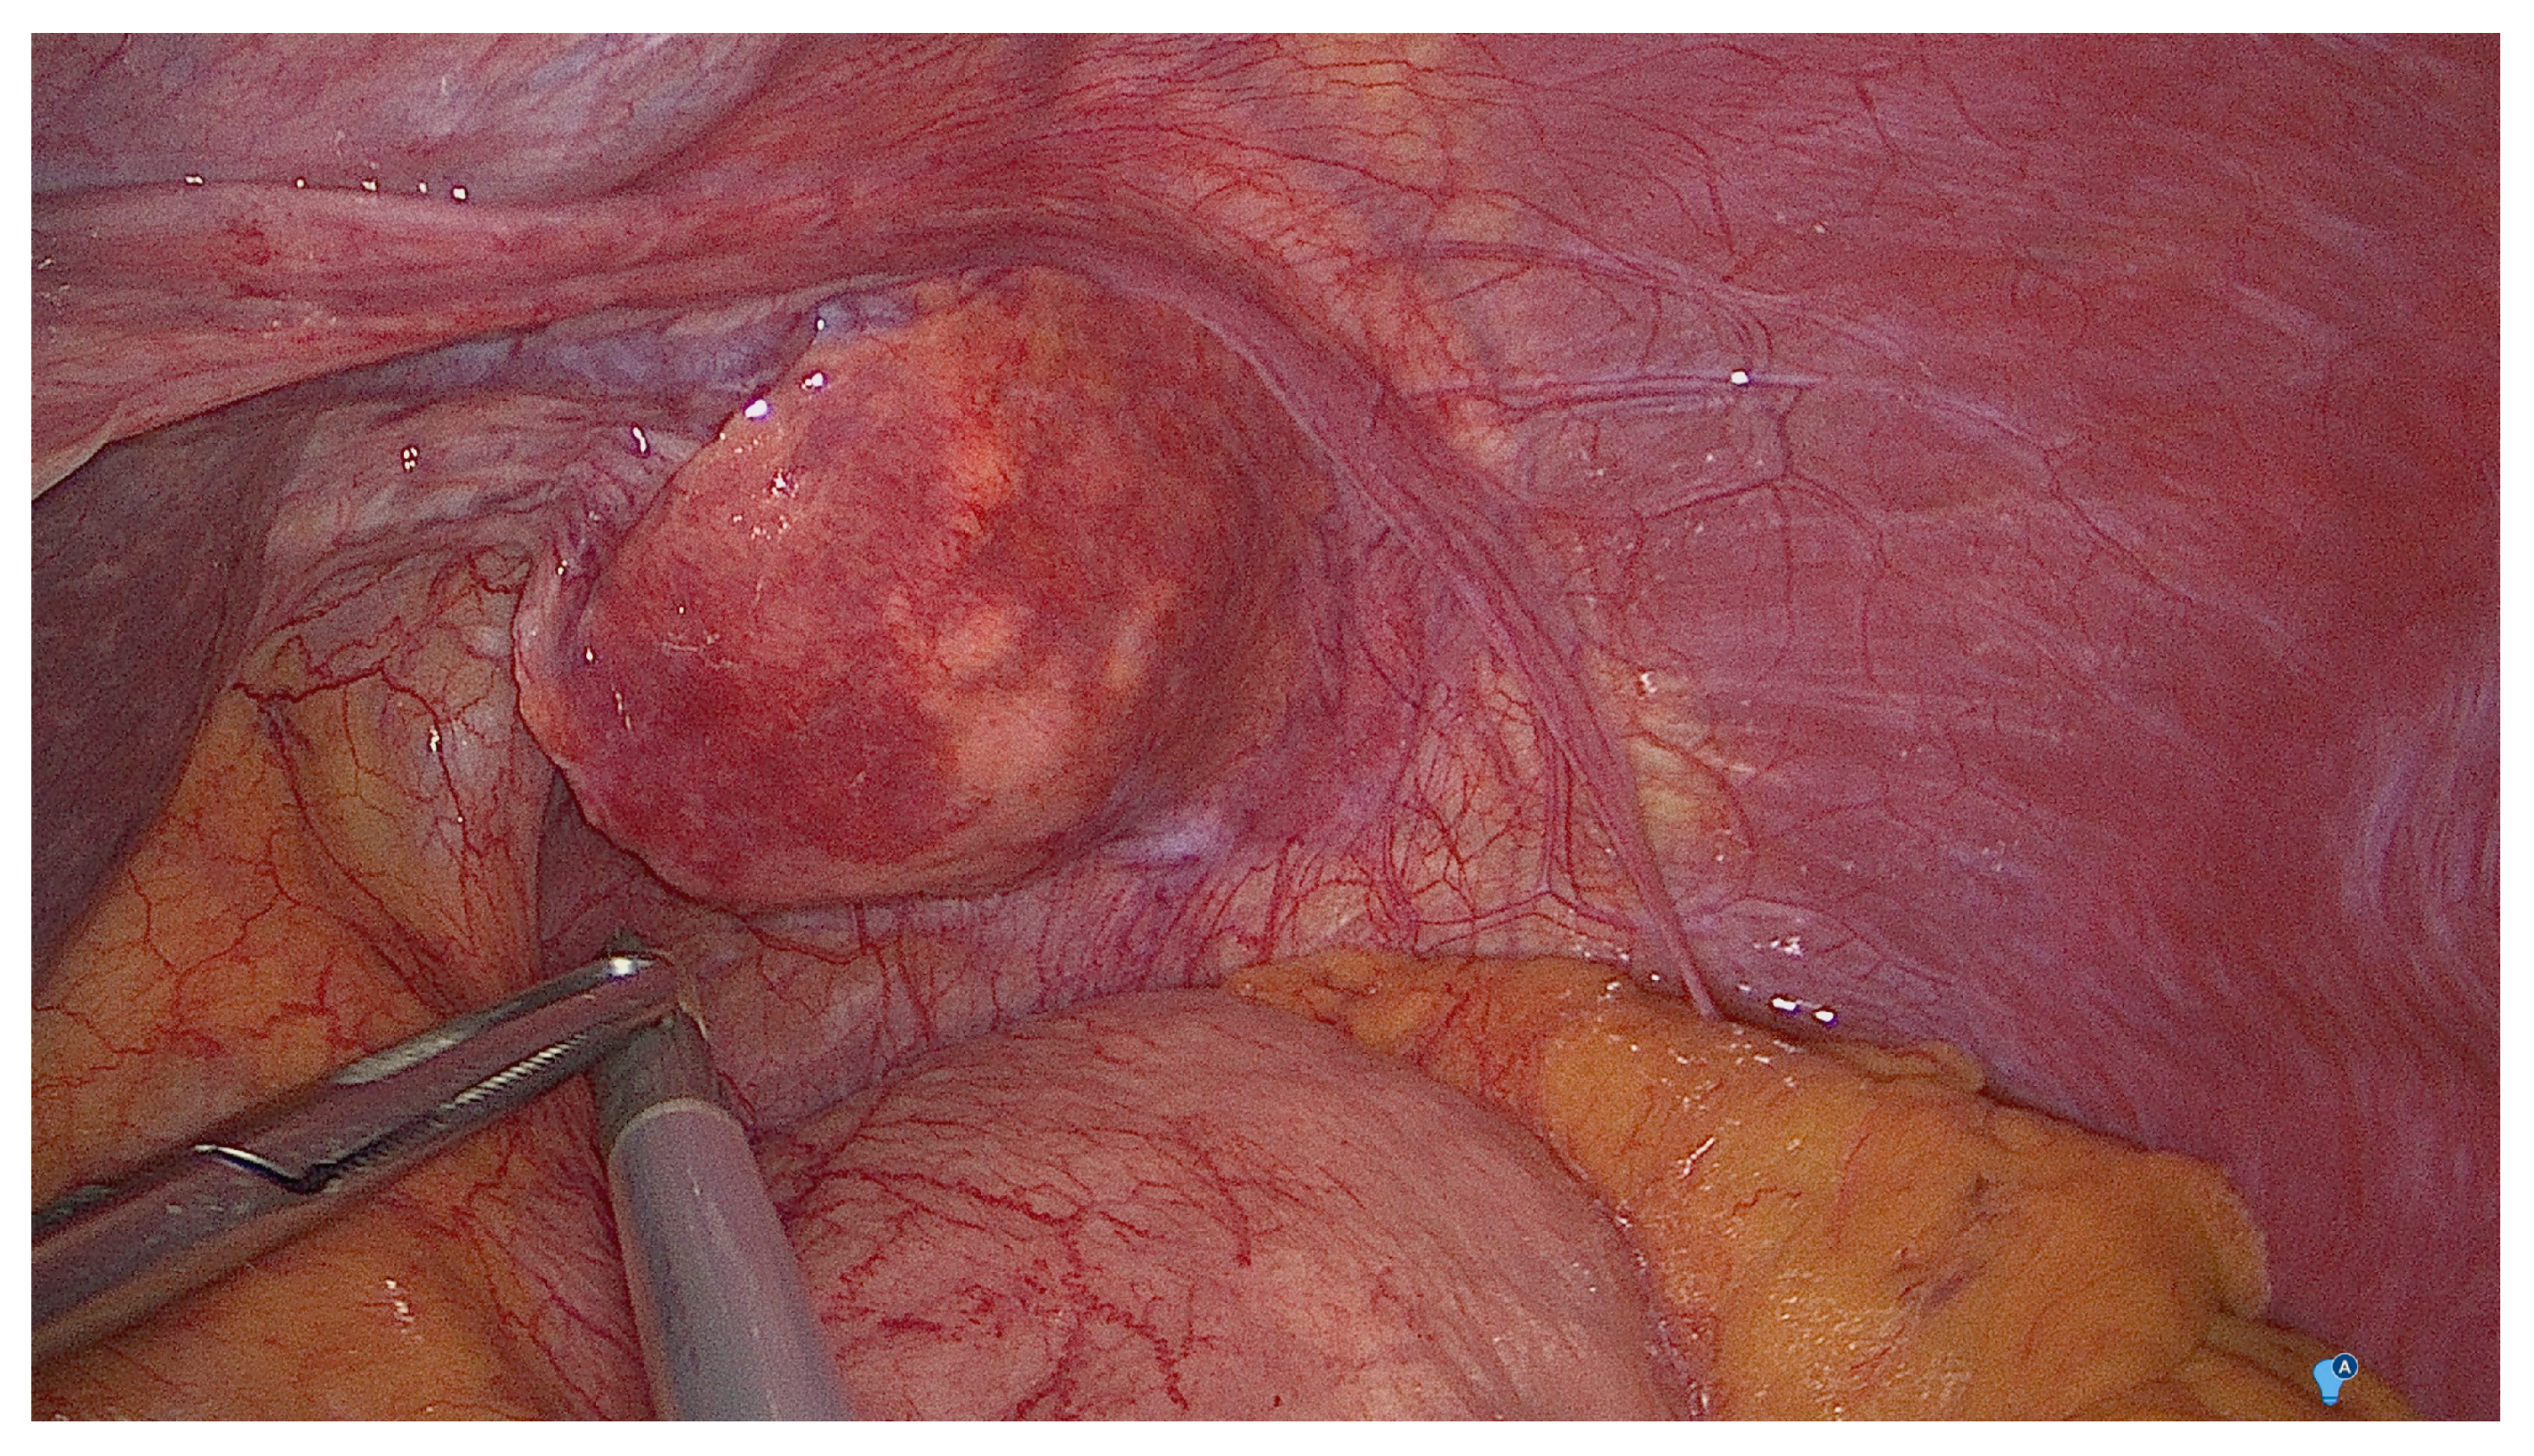

2. Case Report